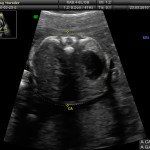

L’ecografia è una tecnica che consente di vedere gli organi del nostro corpo con l’utilizzo di onde sonore ad alta frequenza (ultrasuoni, non udibili dall’orecchio umano) che attraversano i tessuti. La sonda ecografica invia impulsi di onde sonore nel corpo. Quando le onde sonore arrivano al feto mandano degli echi: tali echi (o onde di ritorno) sono trasformati in immagini sul monitor dell’ecografo. Con l’ecografia è quindi possibile osservare in modo dettagliato il feto.

Dal secondo trimestre si misurano altre parti fetali, ed i valori di tali misure vengono confrontati con quelli delle curve di riferimento. Si può così valutare la normalità o meno della crescita fetale. Inoltre periodo si visualizzano la sede di inserzione placentare e la quantità di liquido amniotico.

- E’ possibile rilevare con l’ecografia anomalie fetali maggiori?

La possibilità di rilevare un’anomalia maggiore dipende dalla sua entità, dalla posizione del feto in utero, dalla quantità di liquido amniotico e dallo spessore della parete addominale materna; perciò è possibile che talune anomalie fetali possano non essere rilevate all’esame ecografico. Inoltre alcune malformazioni si manifestano tardivamente (al 7°- 9° mese) e perciò non sono visualizzabili in esami precoci. L’esperienza finora acquisita suggerisce che un esame ecografico routinario, non mirato, consente di identificare dal 30 al 70% delle malformazioni maggiori. Non è compito dell’ecografia la rilevazione delle cosiddette anomalie minori (Linee Guida SIEOG 2006).